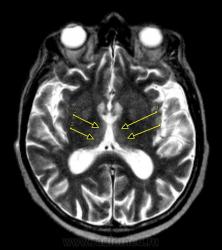

Пациент – Мужчина 60 лет, сельский житель. В анамнезе – злоупотребление алкоголем. Заболевание начиналось постепенно, прогрессировало в течении нескольких дней. Вел себя неадекватно, потом постепенно впал в кому. Направлен на МРТ для исключения объемного образования. Через несколько дней после исследования умер. Родственники от вскрытия отказались, так что загадка остается до конца не разрешенной. На томограммах определяются симметричные участки повышенного на Т2 ВИ и TIRM сигнала в медиальных отделах зрительных буг ров, без признаков контрастного усиления. Хотелось бы узнать мнение коллег.

Наиболее вероятно - отравление. Вот только чем - это вопрос. Нужно расспросить родственников, что он мог выпить помимо магазинных напитков. Широко распространены случаи выпивания автомобильной "незамерзайки" и т.п. Симметричные поражения как раз характерны для таких интоксикаций.

Жена стоИт на том, что пил только водку "качественную", мол пенсия была хорошая. Я честно говоря думаю либо энцефалопатия Гайе-Вернике (или еще что-то дисметаболическое) либо действительно интоксикация.

Я думаю об о. алкогольной энцефалопатии Гай-Вернике-обусловенной дефифитом вит В1. Прогноз засисти от своевременно начатого лечения. Необходиом ведение больших доз тиамина.

К сожалению прогноз уже ни от чего не зависит, помер мужик . Хотя я и поставил Гайе-Вернике на первом месте в диф. ряду. Даже написал в скобочках пояснение, что это обусловлено, мол дефицитом вит. B1 (никогда не знаешь к каким клиницистам попадет пациент и знают ли они что такое энцефалопатия Гайе-Вернике). Увы.